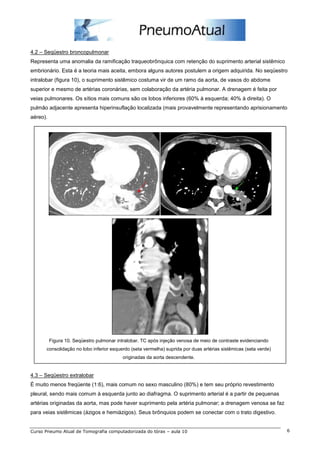

3.1 – Drenagem venosa pulmonar anômala

Resulta num desvio do fluxo sanguíneo esquerdo-direito, com o sangue venoso pulmonar fluindo

diretamente para o lado direito do coração ou para veias sistêmicas (figura 7). Pode ser parcial ou total.

Figura 7. Drenagem venosa pulmonar anômala. TC em planos axiais seqüenciais evidenciando veia pulmonar superior

direita (seta vermelha) drenando para a veia cava superior (seta verde).